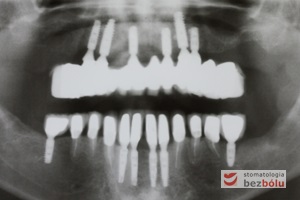

Radiologiczna kontrola osiągniętego efektu terapeutycznego